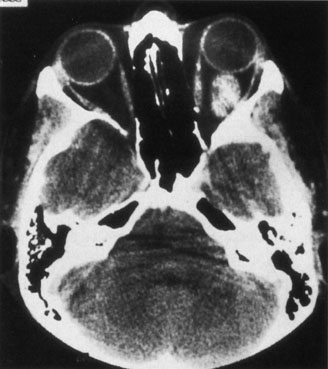

Contrast-enhanced CT of the orbits with direct and coronal cuts is the radiologic study of choice for these patients.45 A well-demarcated, encapsulated oval or rounded mass is revealed, which is typically intraconal in the lateral part of the middle third of the orbit (Fig. 5) but occasionally may extend to the extraconal space.42 Septa within the tumor may be apparent on high-resolution CT. The posterior pole of the globe frequently is indented by the rounded anterior margin of the tumor.42 The optic nerve typically is displaced rather than surrounded by the tumor. Subtle outward bowing of the lateral orbital wall or increase in orbital size may be present, consistent with a long-standing, slowly growing mass lesion.10,42 Enhancement with intravenous contrast occurs and may be homogeneous or inhomogeneous.10,45 Rarely, cavernous hemangiomas may occur as an intraosseous tumor within the orbital or facial bones.42,53–55 Although usually an isolated intraorbital lesion, multiple lesions in one orbit occurred in 8 of 164 (5%) patients of three combined large studies,10,42,45 and bilateral multiple cavernous hemangiomas also have been described.56 In contrast to patients with venous flow malformations in which phleboliths are common, phleboliths are rare in cavernous hemangiomas. Three large studies comprising 164 patients with cavernous hemangioma all reported that no calcification was detected within the tumor.10,42,45If the diagnosis is still unclear or if better definition of details and localization of the lesion is required, then MRI should be performed. Magnetic resonance imaging demonstrates nonspecific characteristics of a lesion isointense to muscle and gray matter on T1-weighted images and hyperintense on T2-weighted images (Fig. 6).57 The lesions show initial central patchy enhancement, which fills up homogeneously within 20 to 60 minutes.58 If ultrasonography is performed, B-scan ultrasonography shows a well-circumscribed mass with a sharply defined anterior acoustic border.23 A-scan ultrasonography shows high reflectivity of the echo signals resulting from the multiple blood-filled vascular channels, regular internal structure with a higher anterior and posterior spike marking the capsule, and moderate sound attenuation (angle of decrease of the echo spike within the lesion).24 Arteriography is not indicated.

Fig. 6. Cavernous hemangioma. Axial magnetic resonance imaging demonstrates a well-defined, homogeneous intraconal mass that is isointense to muscle and gray matter on T1-weighted image (A), and hyperintense on T2-weighted image (B). Note the displacement of the optic nerve and indented posterior globe.